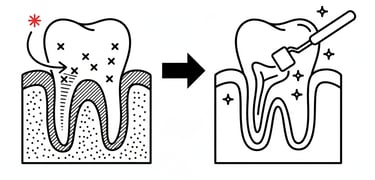

Ενδοδοντική θεραπεία (Απονεύρωση)

Η ενδοδοντική θεραπεία επεμβαίνει στο εσωτερικό του δοντιού (τον πολφό), όπου βρίσκονται νεύρα και αγγεία. Σκοπός της είναι να αφαιρεθεί ο μολυσμένος ή φλεγμονώδης ιστός, να καθαριστούν και να σφραγιστούν οι ριζικοί σωλήνες, ώστε να σωθεί το δόντι και να εξαλειφθεί ο πόνος ή η λοίμωξη.